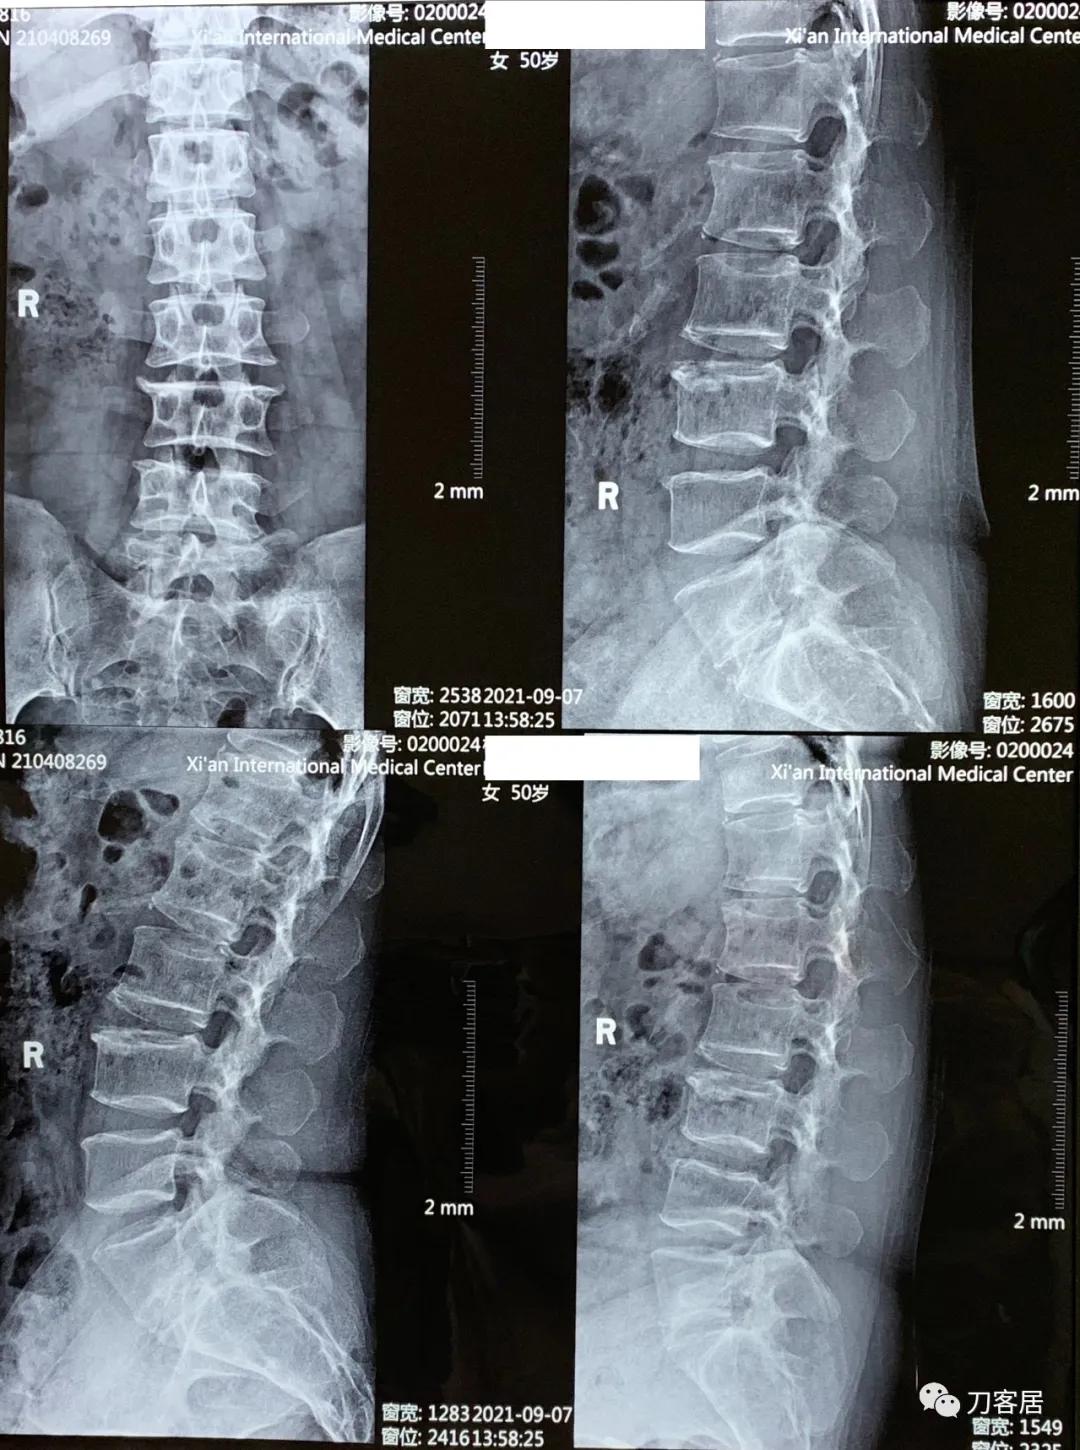

图1. 20210907西安国际医学中心腰椎正侧及过伸过屈位X线片, 提示骨质疏松,腰椎侧弯,骨质增生。过伸过屈位X线片提示腰椎稳定性尚好。